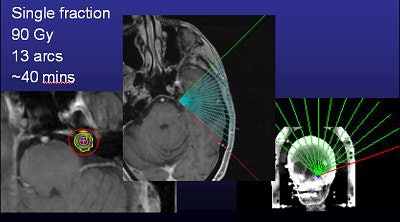

Murphy and colleagues at UCSD work with a linac system (Trilogy) and also perform gamma knife surgery. Time is one major difference between the two options in TN. A procedure with the Trilogy system takes about 30 to 40 minutes versus about two to three hours with the gamma knife, he said.

Murphy's list of linac shortcomings is, well, short. "I trained on (gamma knife). To train on a (Trilogy) system that was frameless and not proven was a hard thing to do. The dose is really high (90 Gy, four times the regular radiotherapy dose, but the same as gamma knife), and it's right next to the brain stem, so if you miss or the patient moves, you're going to fry the brain stem," he said.